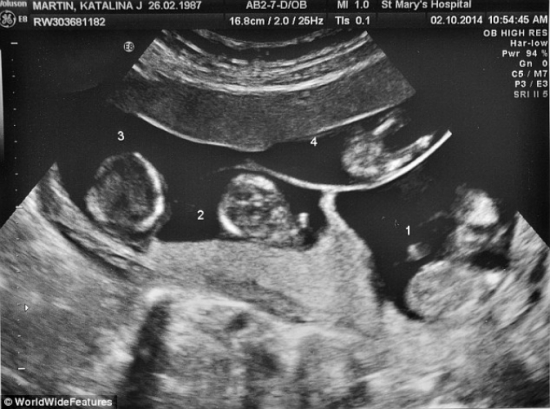

Bào thai được quét qua màn ảnh khi siêu âm đã dự đoán cô có khả năng sinh 3 hoặc sinh 4

Điều bất ngờ là chỉ vài tháng sau đó, cô phát hiện mình mang thai. Cô thực hiện siêu âm tại bệnh viện Stepping Hill ở Stockport. "Tôi đã bật khóc khi bác sĩ nói rằng đây có thể là một ca sinh ba hoặc sinh tư" - cô Martin chia sẻ.